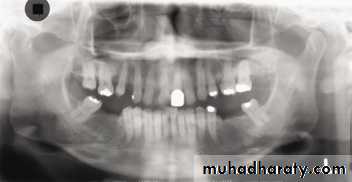

Upper orthodontic appliance

Panoramic Radiography